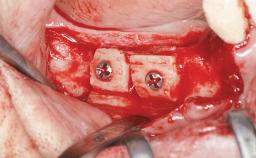

Iliac and Calvarial Bone Blocks for Onlay Grafting of a Severely Resorbed Edentulous Maxilla

| Bone Augmentation | Horizontal|Sinus Floor Elevation|Staged|Vertical |

| Augmentation Materials | Autogenous chips|Autogenous block(s) |